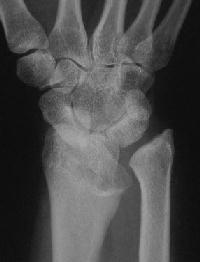

Clinical Example: Madelung's deformity

Madelung's deformity is a dysplasia of the radius resulting in an exaggerated radial inclination, a short forearm, dorsal dislocation of the ulnar head and a "V" shaped proximal carpal row. It may be painful and may result in extensor tendon rupture. Congenital Madelungs may be due to an abnormal fibrous band tethering sigmoid notch of the radius proximally to the ulna. Traumatic Madelung's may follow partial growth arrest of the distal radius. Treatment options differ in the mature and immature skeleton.

Case 1. Typical Xray findings of congenital Madelungs.